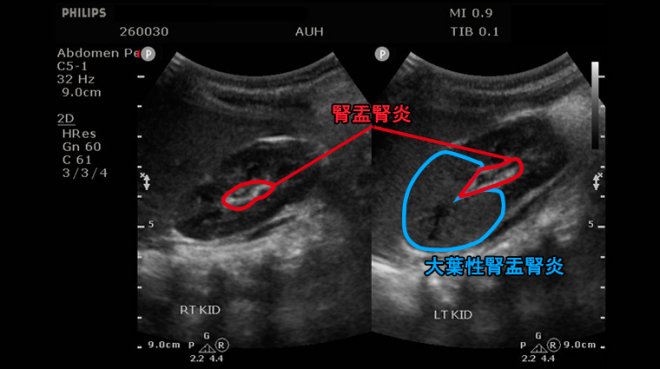

安排腎臟超音波檢查發現雙側腎盂腎及左腎前端實質發炎,留取尿液培養後確診為大腸桿菌引起的左側「急性大葉性腎盂腎炎」及雙側「急性腎盂腎炎」,經靜脈注射抗生素治療7天後才順利出院,但因為大葉性腎盂腎炎屬較嚴重的泌尿道感染,出院後仍需持續使用有效的抗生素治療3周以上。

▲1歲以下的孩子發生泌尿道感染時症狀並不明顯,因此若出現發燒症狀通常疾病已進展至急性腎盂腎炎(APN),嚴重時可能惡化為急性大葉性腎盂腎炎(ALN)。(圖/亞洲大學附屬醫院提供)